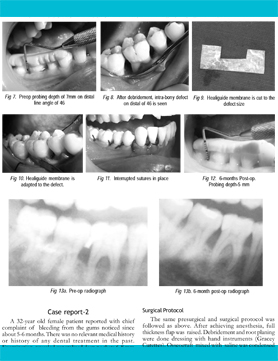

HEALIGUIDE ® (Bioresorbable GTR/GBR Membrane)

Management of Mucosal Fenestration and Palatogingival Groove (2015)